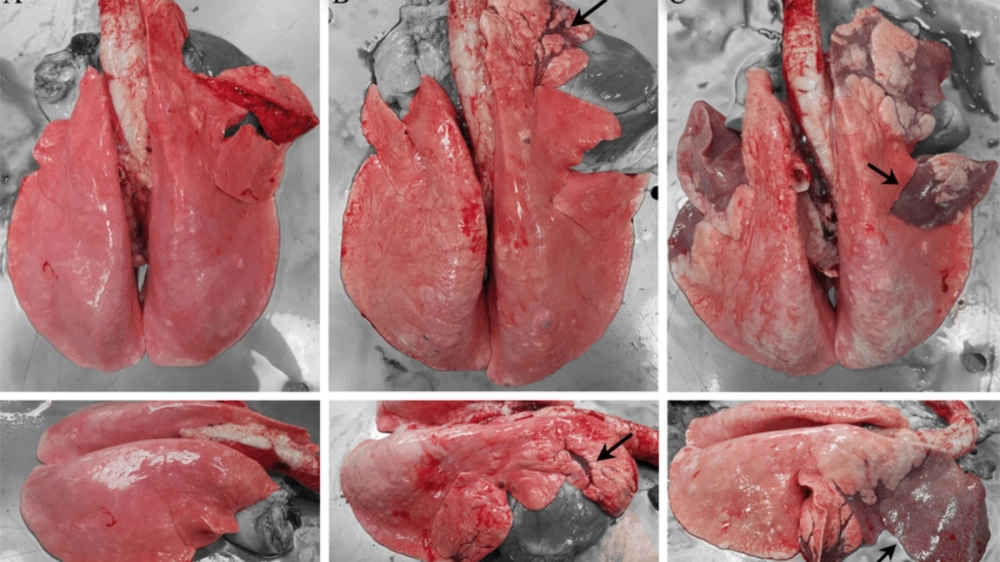

Tổng hợp các hình ảnh về bệnh viêm phổi trực quan nhất